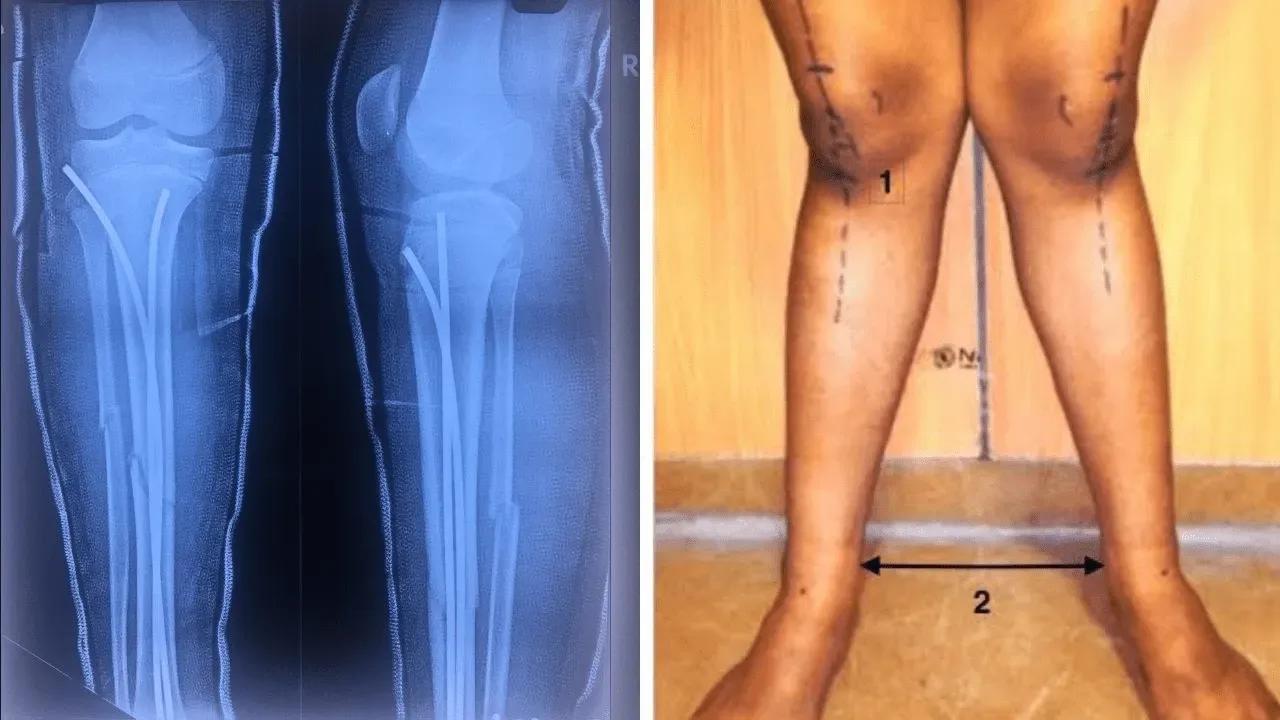

Pediatric Care: Takes care of children with bone issues like fractures, bow legs, and knock knees with gentle and expert treatment.